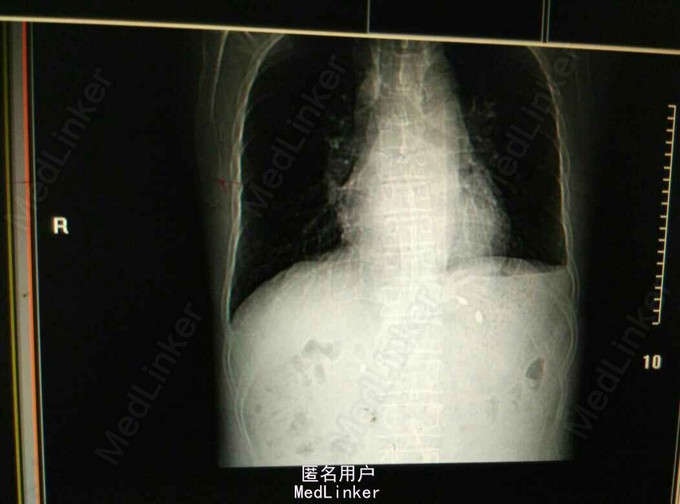

黑便1天。患者男,48岁,因黑便1天入院。患者于1天前驾驶后出现黑便,约200-300ML,急诊查大便潜血:阳性。入院时症见:神清,精神一般,无腹胀,大便色黑,稀烂。患者既往有乙肝病史10年余,肝硬化病史7年余。

查体:生命体征平稳,心肺未见异常。腹部无膨隆,无腹壁静脉曲张,无移动性浊音。血分析:WBC 3.55X10^9/L,Hb 72g/L。肝功能:AST 103U/L,ALT63U/L。电解质:正常。肝胆B超示:肝实质回声明显增强;肝内小囊肿可能;胆囊壁毛糙,胆囊结石声像。